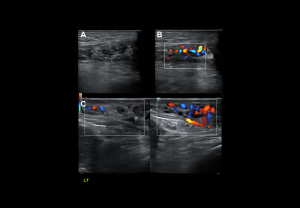

DOPPLER EVALUATION

Assessment of testicular perfusion is a critical component in acute scrotal pain.

Technical optimization:

- Use the lowest velocity scale and low wall filter to detect slow flow.

- Maximise colour gain for sensitivity, avoiding excessive noise.

Flow characteristics:

- Intratesticular arteries: Low-resistance waveform with continuous diastolic flow; peak velocities 3–5 cm/s; RI 0.4–0.7.

- Cremasteric and deferential arteries: High-resistance patterns.

- Veins: Non-pulsatile, low-velocity continuous flow.

- Centripetal and transmediastinal arteries: Low-resistance patterns.